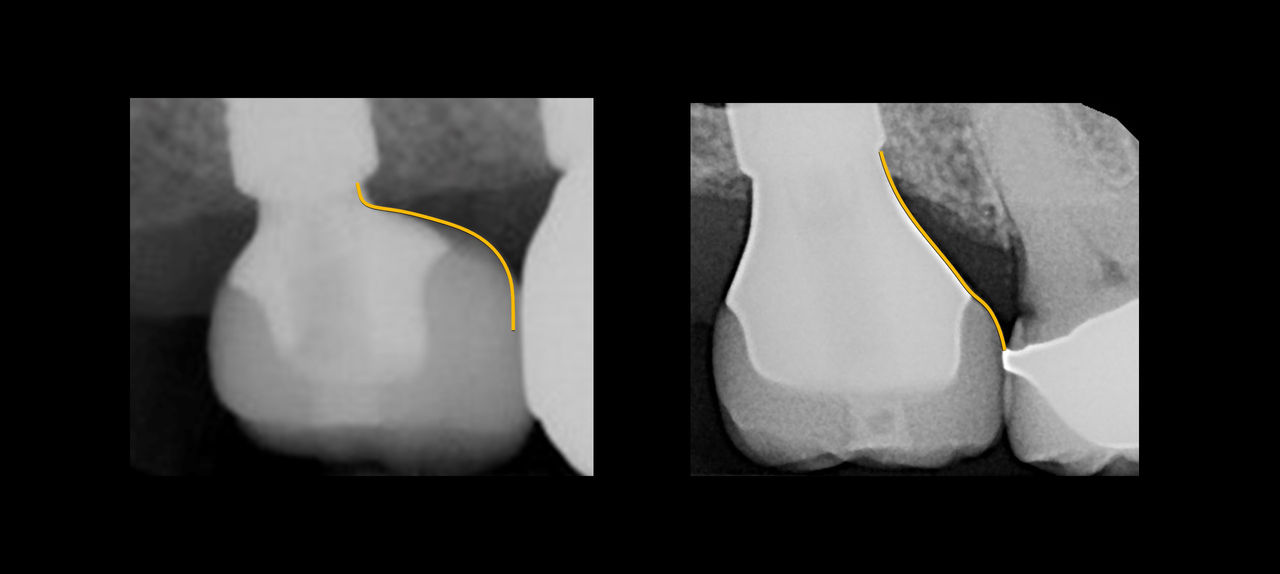

This mastery-level course discusses both the prevention and management of surgical and restorative complications. Within the surgical realm, the presentation focuses on early implant failure and later peri-implant disease. Prosthetic concepts will involve preventative prosthesis design, screw/abutment removal, and sequencing that acknowledges the importance of patient experience.

The implant curriculum is an interactive, procedure-based series of courses that use individual cases to teach current implant treatment. This approach is in contrast to conventional dental education that focuses more on didactic topics and theory. The purpose of using this educational approach is to highlight the patients and procedures found in everyday clinical practice, where the most important concepts are observed and discussed in multiple clinical scenarios.